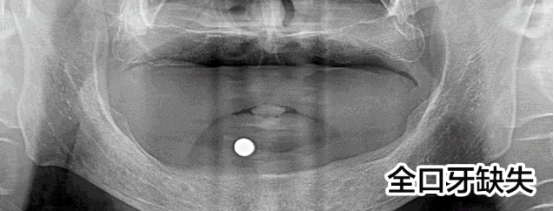

先天性牙缺失修復案例

趙先生先天性發(fā)育異常導致全口牙缺失,才36歲就掉了好幾顆牙,為此趙先生痛苦:“聽說這是一種病,發(fā)病概率小,但不知道怎么就被我攤上了。我還這么年輕就缺了這么多顆牙,真的很奔潰!”

趙先生的遭遇讓人同情,他尋找了多家醫(yī)院都被告知他由于牙齒缺失沒有進行及時修復導致他的牙槽骨萎縮,再加上本身骨量不足,無法進行牙齒種植。牙齒的問題讓趙先生一度有了輕生的念頭。而這次他通過新聞知道亞洲種植牙大師劉斌元教授來到福州,就抱著希望來到科爾。

劉斌元教授在為趙先生進行一系列的檢查后說:“這位患者要做種植牙手術的話的確復雜,但是也并非說不能種植,就是操作起來難度大?!?

趙先生的手術順利,種植牙齒后他覺得整個人都活過來了。

“當時只是覺得人很舒服,一下子就放松了,之后腦子就是一片空白,手術進行的很快,從進入種植間到至后一顆種植牙的植入,只用了短短3個小時”,三分鐘改變了趙先生的一生,趙先生感激劉斌元教授:“如果沒有劉斌元教授為我進行手術,我都不知道接下來該怎么辦?,F在說什么都不能表達我的感激之情,但還是要對劉院長說一聲謝謝!”

首先,像趙先生這樣的先天性發(fā)育不良造成的全口牙缺失的病例本身就是很罕見的,可以說是幾十年難遇。其次,全口牙缺失本身就屬于牙科領域中難的一種技術。沒有先進的高精口腔CT技術的保障,在傳統(tǒng)的診療條件下,很難手術的。因而,在硬件、設備、技術還不成熟的情況下,并不是所有醫(yī)院都能完成這種病例的調節(jié)。因此,在做全口牙種植前,選擇正規(guī)的醫(yī)院和臨床經驗豐富的醫(yī)生,是保障手術成功的先決條件。